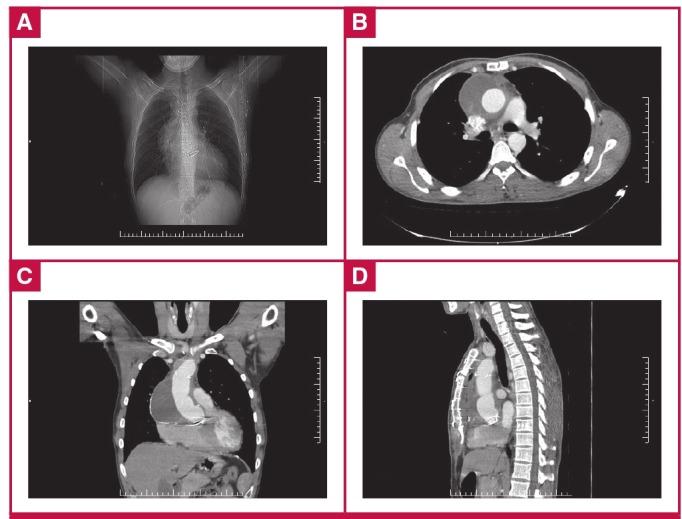

Giant aortic aneurysm is defined as an aneurysm of the aorta of greater than 10 cm in diameter. This rare condition is associated with a high risk of morbidity and mortality and it may lead to fatal complications such as rupture and/or dissection if not managed with proper surgical planning and expertise. Other than atherosclerosis, the main causes of giant ascending aortic aneurysms include Marfan and Ehlers-Danhlos syndromes. Herein we report on a young male patient who had had an aortic valve replacement five years earlier due to a bicuspid aortic valve leading to aortic failure, accompanied by aortic coarctation. He had an aneurysmal expansion rate of 1.81 cm/year to reach a final aneurysmal diameter of 13.25 cm, which, to our knowledge, represents the largest size ever reported in the literature for such lesions, and in which the redo and aneurysmal wall were adjacent to the sternal margins.

巨大主动脉瘤被定义为直径大于10厘米的主动脉瘤。这种罕见病症与高发病率和死亡率风险相关,如果没有适当的手术规划和专业技术进行处理,可能会导致诸如破裂和/或夹层等致命并发症。除动脉粥样硬化外,巨大升主动脉瘤的主要病因包括马凡综合征和埃勒斯-当洛综合征。在此,我们报告一名年轻男性患者,他五年前因二叶式主动脉瓣导致主动脉功能衰竭并伴有主动脉缩窄而接受了主动脉瓣置换术。他的动脉瘤扩张速率为每年1.81厘米,最终动脉瘤直径达到13.25厘米,据我们所知,这是此类病变在文献中报道的最大尺寸,并且再次手术区域和动脉瘤壁紧邻胸骨边缘。